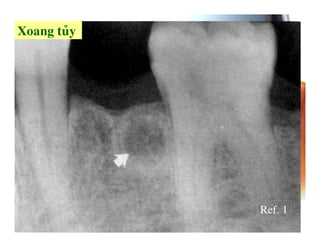

Ref. 1